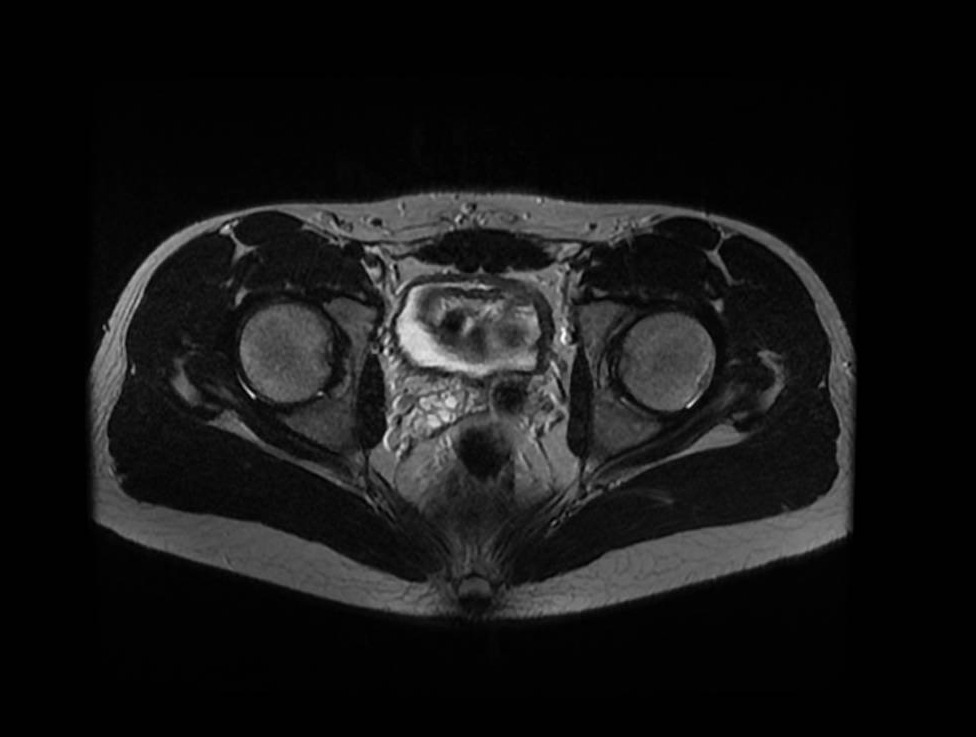

At age 16, a follow-up ultrasound identified asymmetry in the seminal vesicles, indicating congenital agenesis of the left seminal vesicle. Suspecting Zinner syndrome, an abdominal-pelvic magnetic resonance imaging (MRI) was performed, confirming left renal agenesis (Figure 1), ipsilateral agenesis of the seminal vesicle (Figure 2) along with a periurethral cyst (Figure 3) and a hypotrophic left testicle, thus confirming the diagnosis. The patient reported no abdominal, pelvic or testicular pain and no lower urinary tract symptoms. Clinical, imaging and laboratory follow-up were maintained, with the patient remaining asymptomatic throughout and retaining a glomerular filtration rate within the normal ranges.

Figure 2. Axial T2-weighted MRI of the pelvis demonstrating agenesis of the left seminal vesicle.

Figure 3. Axial T2-weighted MRI of the pelvis demonstrating a periurethral cyst.